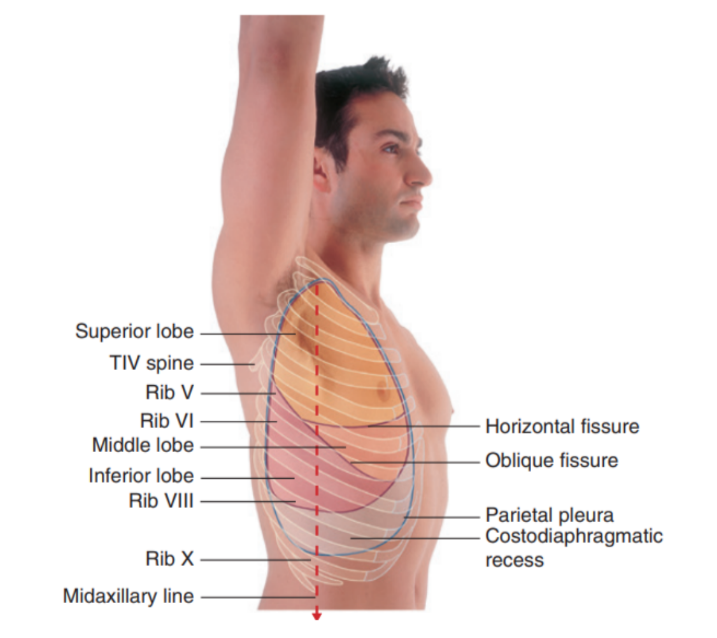

Surface anatomy relating to the fissures and lobes

Palpable surface landmarks —

Can be used to visualize the normal outlines of the pleural cavities & lungs & to determine the positions of the pulmonary lobes & fissures —ex.

Superiorly, we can see the parietal pleura projects above the first costal cartilage & anteriorly approaches the midline posterior to the sternum (uppermost section). Left parietal pleura doesn’t come close to the midline as much as the right lobe due to the heart bulging on the left side

Inferiorly, the pleura reflects on the diaphragm, above the costal margin & courses around the thoracic wall following an VIII, X, XII contour

(Ie. rib VIII in the midclavicular line, rib X in the midaxillary line, and vertebra TXII posteriorly)

Lungs don’t completely fill areas surrounded by pleural cavities — particularly anteriorly & inferiorly —

Costomediastinal recesses —

Occur anteriorly, particularly on the left side in relationship to the heart bulge

Costodiaphragmatic recesses —

Occur inferiorly between the lower lung margin & the lower margin of the pleural cavity

Margins of lungs related to ribs

Inferior lung margin —

Found at bottom of the thoracic wall, following a VI, VIII, X contour (ie. rib VI in the midclavicular line, rib VIII in the midaxillary line, and vertebra TX posteriorly)

Oblique fissure position —

Located in the midline, near the spine of vertebrae TIV, moves laterally downwards crossing fourth and fifth intercotal spaces and reaches VI laterally

Horizontal fissure(right side) —

Follows the contour of rib IV and its costal cartilage

Oblique fissures on both sides follow the contour of rib VI and its costal cartilage